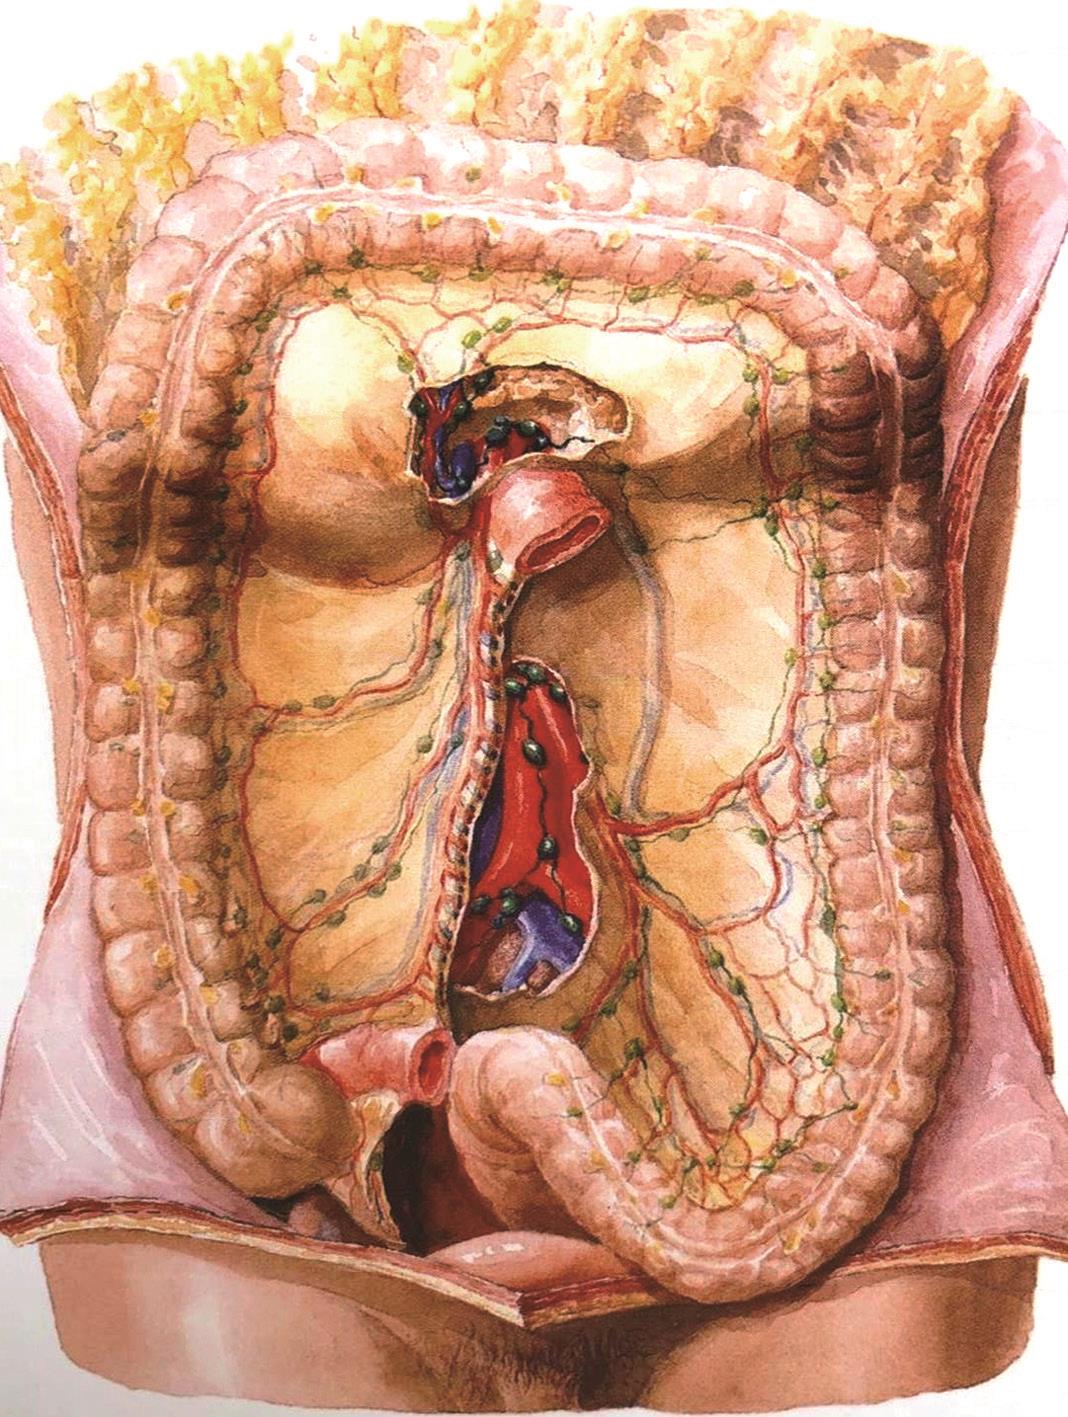

从结肠各段肠壁淋巴液到淋巴管,均循序沿着各自的血管走行,到达相应的淋巴结,然后经肠系膜上动脉根部和肠系膜下动脉根部淋巴结至腹主动脉旁淋巴结,再注入胸导管。各组淋巴结之间及邻近的淋巴结均有广泛联系,回盲部的淋巴还可经胰腺前方到达幽门下淋巴结。

图2-8 结肠的淋巴结

位于结肠壁上的肠脂垂内。

位于结肠系膜缘,伴着边缘动脉分布。

沿着结肠右、中、左动脉分布。

沿着肠系膜上动脉和肠系膜下动脉分布。